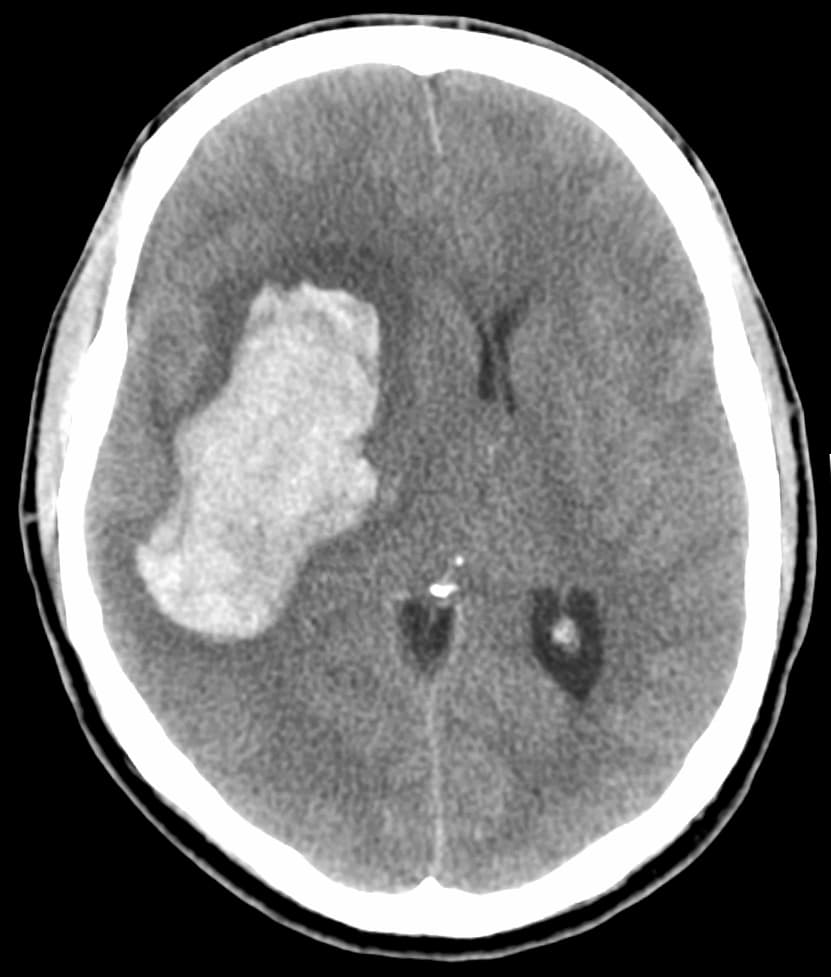

A hypertensive emergency is very high blood pressure with potentially life-threatening symptoms and signs of acute damage to one or more organ systems (especially brain, eyes, heart, aorta, or kidneys). It is different from a hypertensive urgency by this additional evidence for impending irreversible hypertension-mediated organ damage (HMOD). Blood pressure is often above 200/120 mmHg, however there are no universally accepted cutoff values. Signs of organ damage are discussed below. Symptoms may include headache, nausea, or vomiting. Chest pain may occur due to increased workload on the heart resulting in inadequate delivery of oxygen to meet the heart muscle's metabolic needs. The kidneys may be affected, resulting in blood or protein in the urine, and acute kidney failure. People can have decreased urine production, fluid retention, and confusion. Other signs and symptoms can include: Chest pain Abnormal heart rhythms Headache Nosebleeds that are difficult to stop Dyspnea Fainting or the sensation of the world spinning around them (vertigo) Severe anxiety Agitation Altered mental status Abnormal sensations The most common presentations of hypertensive emergencies are cerebral infarction (24.5%), pulmonary edema (22.5%), hypertensive encephalopathy (16.3%), and congestive heart failure (12%). Less common presentations include intracranial bleeding, aortic dissection, and pre-eclampsia or eclampsia. Massive, rapid elevations in blood pressure can trigger any of these symptoms, and warrant further work-up by physicians. Physical exam would include measurement of blood pressure in both arms. Laboratory tests to be conducted include urine toxicology, blood glucose, a basic metabolic panel evaluating kidney function, or a complete metabolic panel evaluating liver function, EKG, chest x-rays, and pregnancy screening. The eyes may show bleeding in the retina, an exudate, cotton-wool spots, scattered splinter hemorrhages, or swelling of the optic disc called papilledema. Many factors and causes are contributory in hypertensive crises.